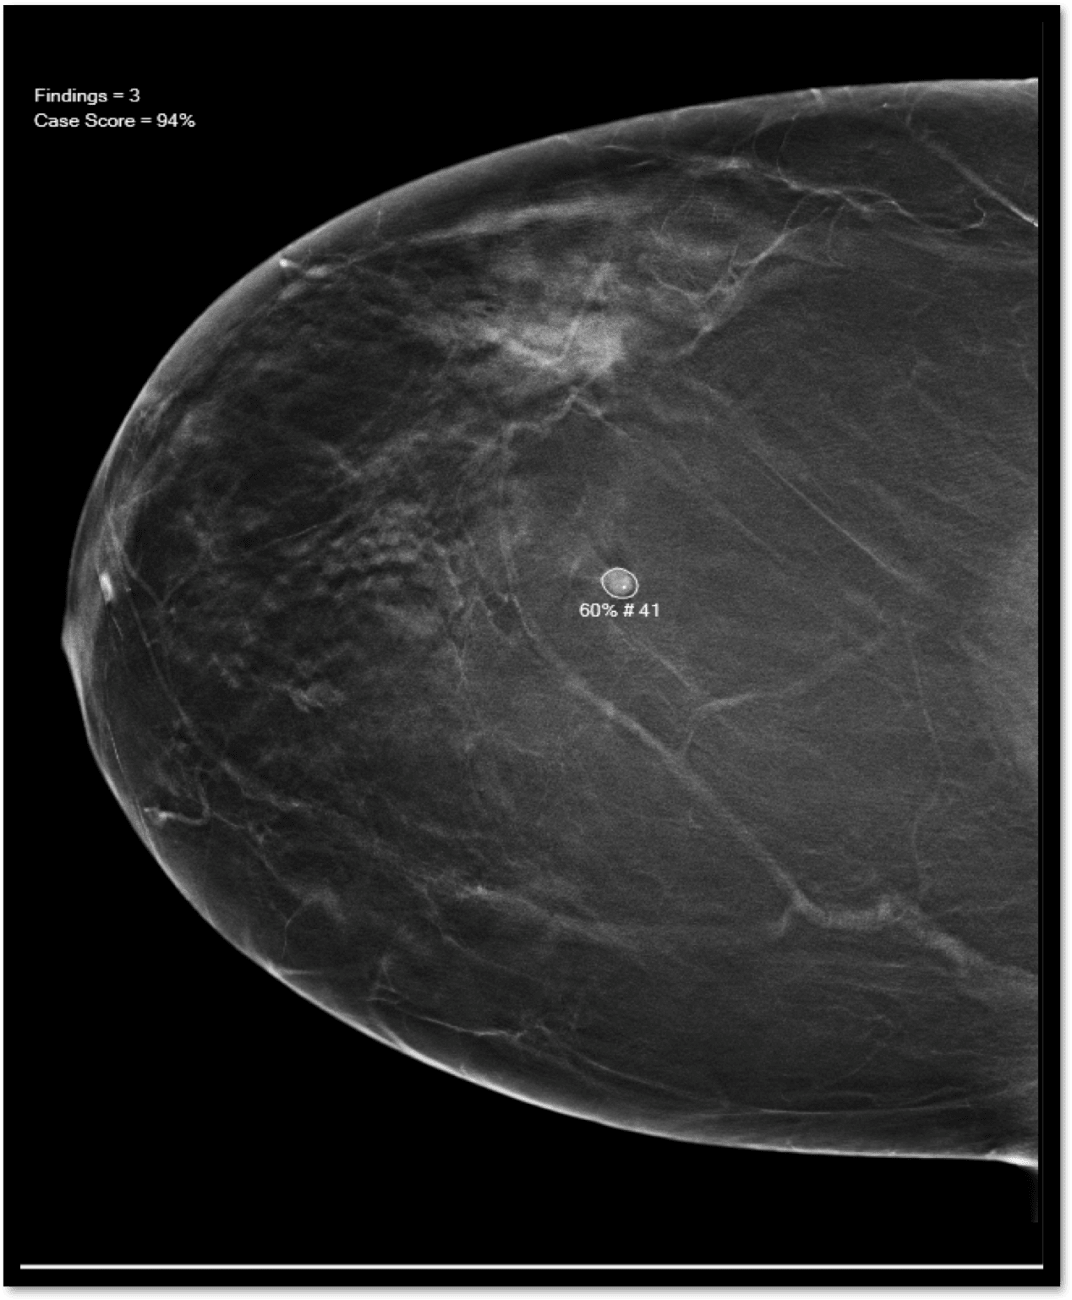

Mammograms remain the standard diagnostic tool for detection of breast cancer. Innovators in the field are now exploring assistive machine learning and articial intelligence (A.I.) to help healthcare providers assess mammograms and detect breast cancers earlier and more efficiently. Dr. Kathy Schilling, MD., Medical Director, Lynn Women’s Health & Wellness Institute, is one of the early adopters of this technology and continues to pave the way for improvements in the field. A.I. technology was first implemented at the Lynn Cancer Institute in 2020 during the COVID-19 pandemic. Dr. Schilling conducted a retrospective evaluation of the institute’s results since adopting this technology, presenting her study findings at the 2023 European Congress of Radiology in Vienna on March 3rd , 2023. Dr. Schilling found that cancer detection rates rose from 5.77 per 1000 women to 7.8 per 1000 women screened. Furthermore, each of the nine dedicated breast radiologists at the center improved in accuracy with a pooled increase of 23%. Dr. Schilling expressed her amazement at the impact A.I. had on her practice. ‘That’s huge, I was so shocked.” said Dr. Schilling. “If you had found 100 cancers before using A.I., we found 123 after using A.I. The increase in number of cancers detected occurred without having an increase in false positives or recalls. We became more accurate in those we recalled."

A.I. systems are trained for specificity and sensitivity in identifying cancer in a mammogram. This is done using hundreds and thousands of images from previous mammograms. Once ready for use, the system can scan the images from a mammogram and notify the radiologist of possible cancer spots. Acting like a second set of eyes. Each image is still examined by the radiologist who utilizes their expertise and a patient’s risk factors to determine if further evaluation is needed. The A.I. system not only reduces the burden on radiologists, who can often get fatigued looking at hundreds of images in a single shift, it also makes it easier to detect possible signs of cancer that the human eye might miss. “This is signicant” says Dr. Schilling. “The types of cancers we are currently finding are smaller and of lower stage, reducing the need for advanced treatments.”